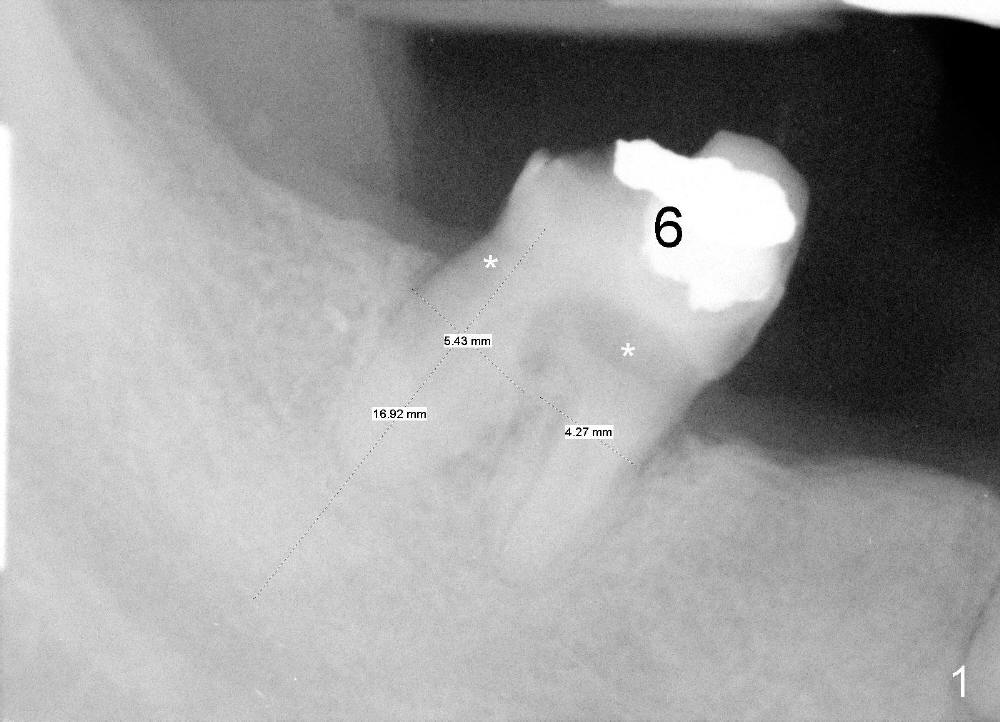

Two weeks later, two of one piece implants are placed at the site of #3 and 4 (3x17), regular two piece implant at #5 (3.5x11; Fig.6).  Fig.7 is taken one week post op.

Four months after implantation, the gingiva around these four implants is healthy (Fig.8).  Healing cuffs are placed over the implants #5 and 6 (Fig.9).  The trajectory for the one piece implants is within normal limit relative to the opposing dentition (Fig.9,10).